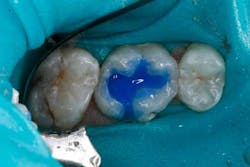

The tooth was prepared and a total etch technique utilizing 37% phosphoric acid was performed (Figs. 3 through 5). After the etchant was rinsed, a desensitizer was placed and blotted to leave a moist dentin surface for bonding (Fig. 6). The bonding agent was applied; the ethanol solvent was air evaporated using a warm air dryer; and the adhesive light-cured for 10 seconds (Figs. 7 and 8).